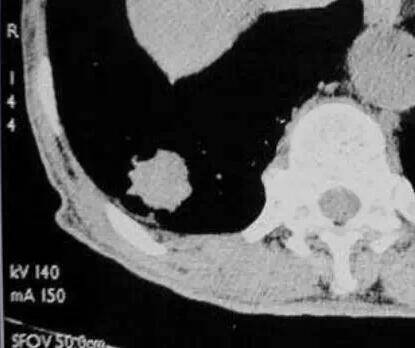

四、胸膜充气征

肿瘤与胸膜之间的线形或三角形影像,发生率约50%,腺癌和细支气管肺泡癌多见。 形成条件:瘤体方向的纤维化收缩,胸膜无增厚粘连,瘤体内纤维化--根本动力。 影响因素:瘤体与壁层胸膜的距离。